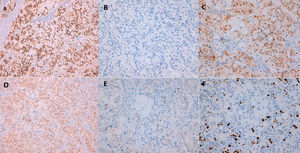

Se practicó biopsia con aguja gruesa guiada por ecografía con el resultado de carcinoma infiltrante de tipo común, grado histológico II (B5b). Se indicó cirugía y, de acuerdo con el paciente, se realizó una mastectomía derecha simple con biopsia selectiva del ganglio centinela axilar. Macroscópicamente el tumor era blanquecino de 1,4cm, nodular, no conectado con la piel o el pezón suprayacente. Microscópicamente, el tumor estaba constituido por células pequeñas, con núcleos redondos y nucléolos generalmente únicos, con amplios citoplasmas claros microvacuolados (fig. 2A). La inmunotinción del antígeno de membrana epitelial (EMA) fue positiva (fig. 2B). El tejido fresco contenía citoplasma lipídico que fue positivo para el rojo oleoso (fig. 2C). El componente sebáceo representaba más del 50% del tumor. La inmunohistoquímica de células tumorales reveló positividad para los receptores de estrógeno (RE) (fig. 3A), los receptores de progesterona (RP) (fig. 3B) y los receptores de andrógeno (RA) (fig. 3C y D). La proliferación de Ki67 fue del 30-35% (fig. 3F) y el HER2 fue negativo (fig. 3E).

El diagnóstico patológico definitivo fue de CSM, grado histológico III, con márgenes libres y un ganglio linfático centinela negativo, pT1c pN0 (sn) (mol-). Se inició el tratamiento adyuvante con letrozol. La paciente se encuentra actualmente libre de enfermedad después de 28 meses de seguimiento.